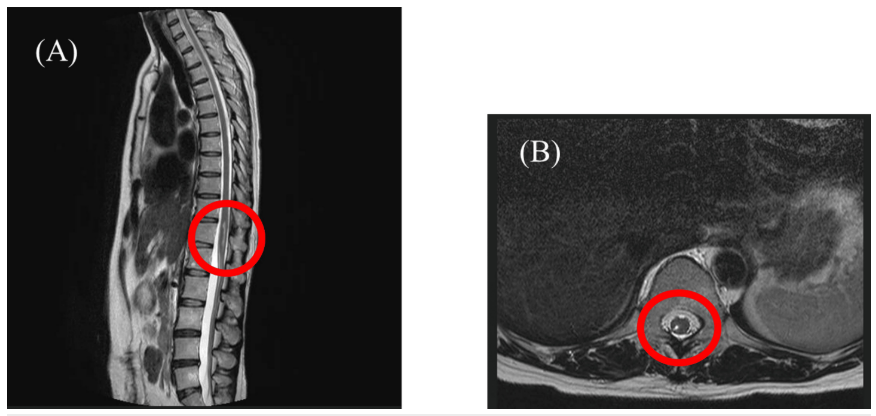

患者为49岁女性(身高151cm,体重53kg,BMI 23.24),主诉右下肢疼痛伴麻木。2021年12月因结肠癌行腹腔镜结肠切除术时接受硬膜外麻醉,术中出现右下肢电击样剧痛,术中至术后留置导管进行镇痛。硬膜外导管拔除后,右下肢持续存在疼痛及麻木症状。T2加权磁共振成像(MRI)通过高信号显像反映组织损伤及水肿导致的水含量增加,本病例显示胸腰段脊髓损伤伴第12胸髓区域积液。因治疗后症状持续存在,患者于2022年5月转至疼痛科就诊。既往史除结直肠癌及卵巢囊肿治疗史外无特殊。初诊时患者自诉右大腿至膝关节疼痛,静息状态下数字评定量表(Numeric Rating Scale, NRS)评分为7/10,发作时达10/10。步态跛行,行走时疼痛最为剧烈。查体发现右下肢肌力减退,踝关节背屈偶发困难。胸腰椎MRI显示T11-T12脊髓水平(右后角至后索)水肿,未见其他脊髓病变或畸形。 脊髓于T11-T12胸椎水平(右后角至后索)呈现水肿影像,未检出其他腰椎病变。(A)矢状面观;(B)横断面观 基于硬膜外麻醉相关脊髓损伤后疼痛的初始判断,但根据患者右大腿至膝关节的局部症状(L3神经根支配区),修正诊断为神经根性疼痛。经硬膜外阻滞联合L3神经根阻滞治疗后,疼痛程度由NRS 5分降至1分,麻木感及足趾不适持续存在,但步态有所改善。该神经根阻滞疗效仅能维持1-3个月。后续启用普瑞巴林(175mg)联合度洛西汀(40mg)治疗,疼痛获得中度缓解(NRS约3分)。鉴于既往治疗仅能暂时缓解症状,患者于初诊后14个月接受脊髓电刺激疗法(SCS),电极置入T8-T9椎体上缘水平。该治疗显著改善疼痛症状,使患者得以开展康复训练并恢复日常活动。病程示意图显示:自初诊起除药物治疗外,虽实施多种神经阻滞但均未获得持久疗效;SCS植入14个月后,疼痛程度稳定于NRS 3分水平。